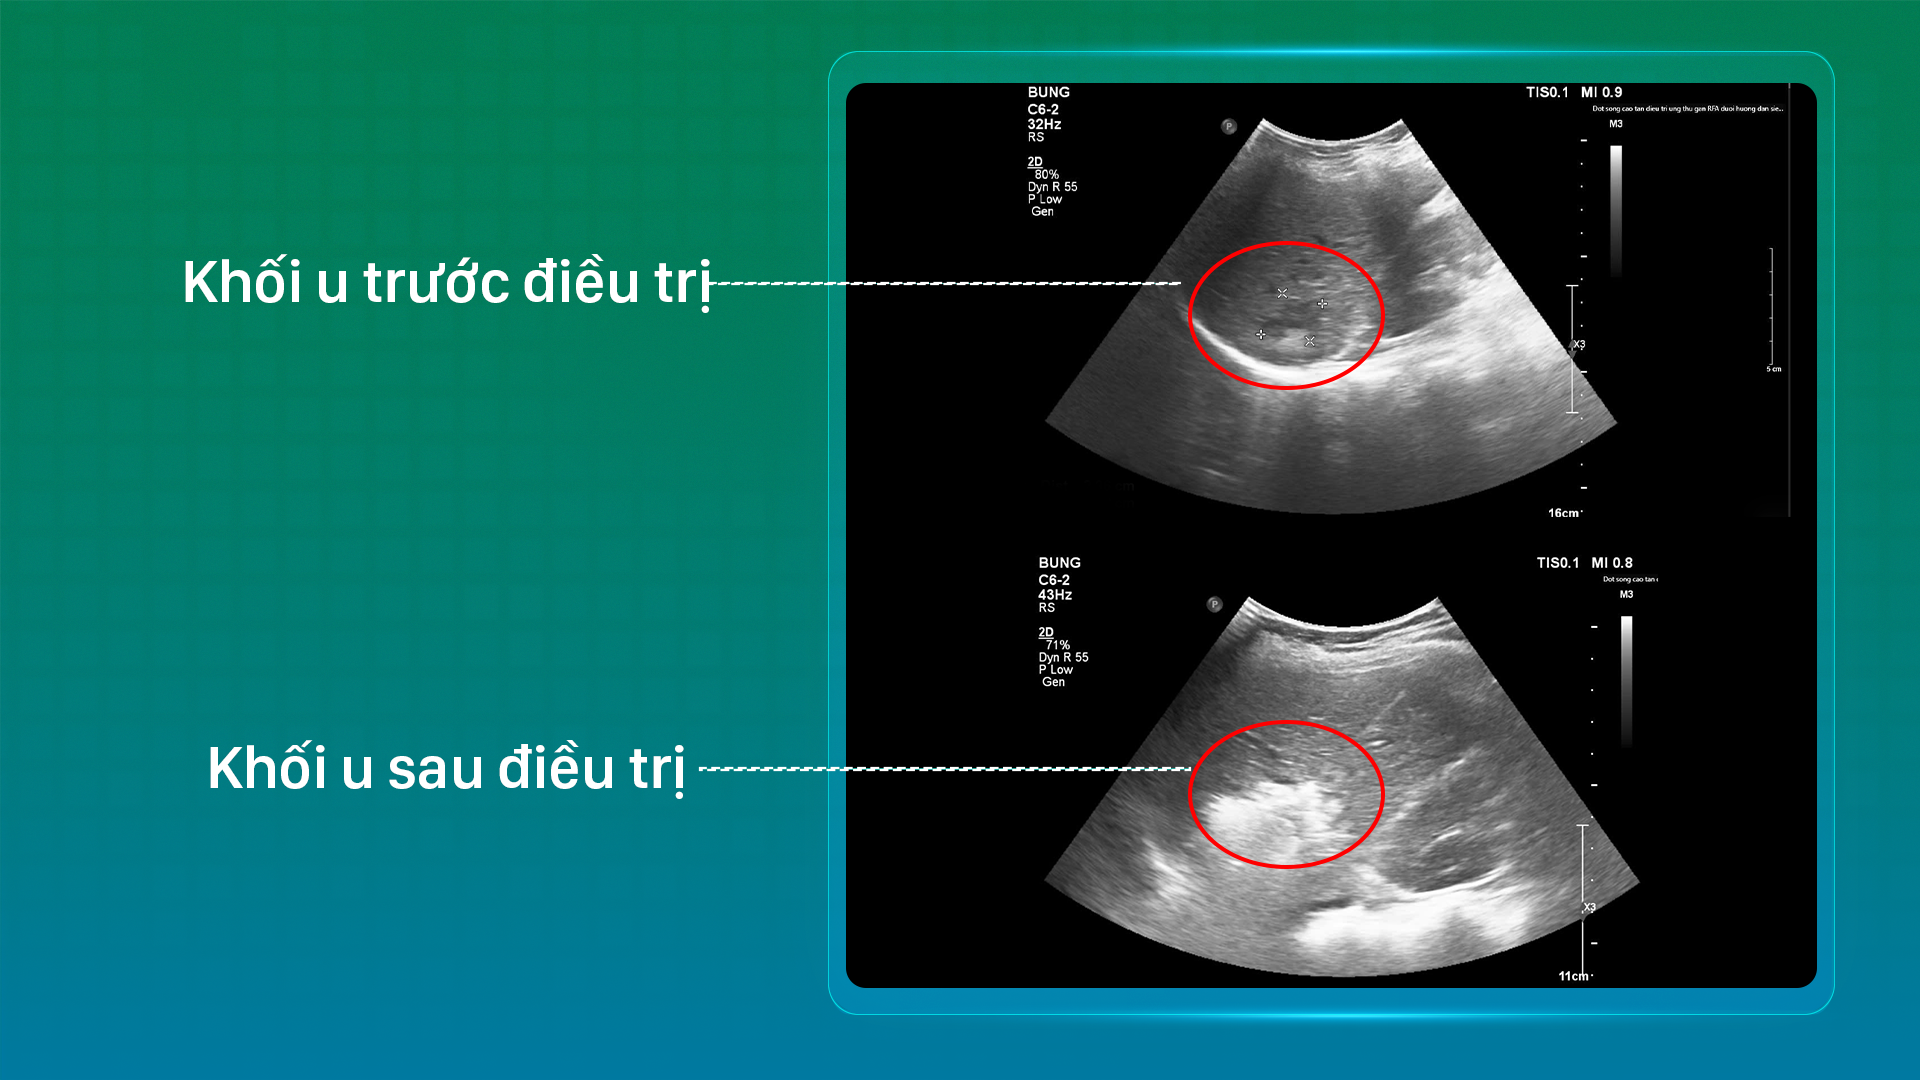

Khối u trước và sau điều trị của bệnh nhân